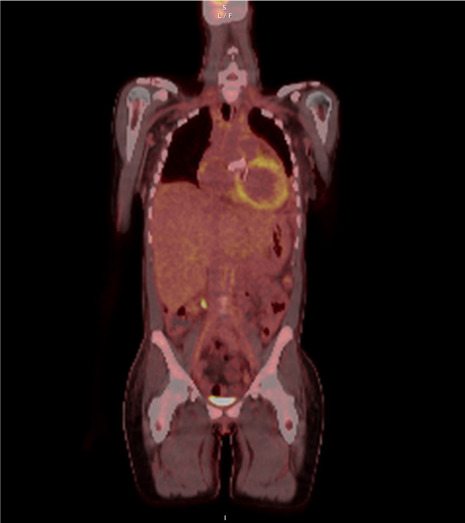

埃尔德海姆-切斯特病是一种罕见的组织细胞增生症,主要影响骨骼系统,但 75% 的病例会出现心血管表现,且预后不良。由于病例较少,该病的演变和治疗尚不确定。因此,报告和分享 Erdheim-Chester 病例非常重要。本报告介绍了一例因埃尔德海姆-切斯特病而患有缩窄性心包炎和二尖瓣反流的年轻患者。

Erdheim-Chester disease is a rare histiocytosis that primarily affects the skeletal system, but cardiovascular manifestations occur in 75% of cases and are associated with a poor prognosis. Given the small number of cases, the evolution and management of the disease are uncertain. Therefore, it is important to report and share Erdheim-Chester cases. This report presents the case of a young patient with constrictive pericarditis and mitral valve regurgitation resulting from Erdheim-Chester disease.